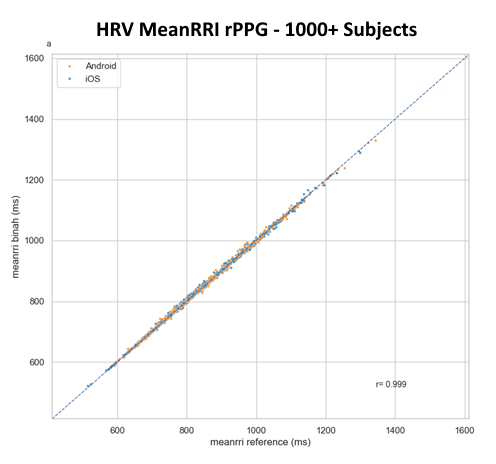

Advanced Heart Rate Variability (HRV) Analysis

Briah.ai’s revolutionary contactless (rPPG) technology delivers precise heart rate variability (HRV) measurements, offering deep insights into autonomic nervous system function and overall cardiovascular health. Our AI-driven solution ensures highly accurate RR interval assessments, validated against reference devices across iOS and Android platforms.

Unlock a new era of remote health monitoring with scientifically validated HRV data—empowering healthcare, wellness, and performance optimization.